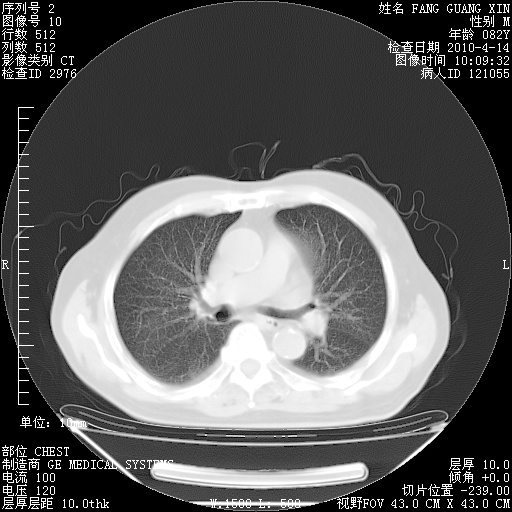

4月14日肺部CT

23.JPG

24.JPG

25.JPG

26.JPG